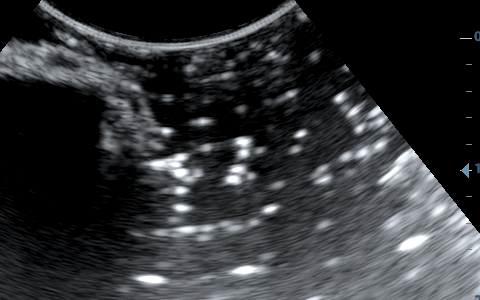

Σημαντικό ρόλο επίσης παίζει η κλίση της βελόνας σε σχέση με τον ηχοβολέα ( κεφαλή ), όσο πιο κάθετη είναι η βελόνα με τον ηχοβολέα τόσο καλύτερη εικόνα της βελόνας έχουμε, όσο αυξάνεται η κλίση τόσο μειώνεται η διακριτική μας ικανότητα.

Λόγω της κλίσης βλέπουμε μόνο την μύτη της βελόνας.

Η βελόνα εμφανίζεται κάθετα προς τον ηχοβολέα.